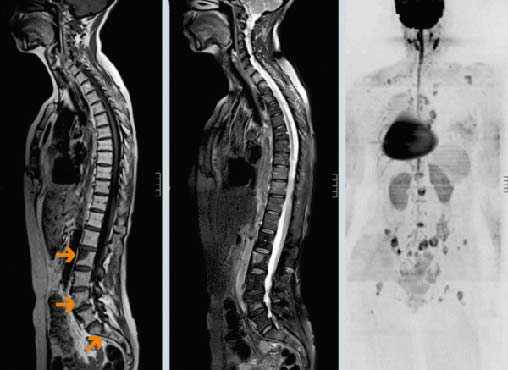

На обзорной рентгенограмме наблюдалась овальная тень с относительно чёткими контурами в головке мыщелка нижней челюсти слева (см. рис. 1). Компьютерная томография и магнитно-резонансная томография выявили объёмное образование левого мыщелка нижней челюсти, медиальную эрозию кости и отёк окружающих структур до крыловидной кости (см. рис. 2—4).

Рис. 1. На обзорной рентгенограмме видна овальная тень с относительно чёткими контурами в головке мыщелка нижней челюсти слева (показана чёрными стрелками). Белыми пунктирными стрелками показаны кальцифицированные шейные лимфатические узлы.

Рис. 2. На компьютерной томографии видны остеолитические процессы в головки мыщелка нижней челюсти слева. Зона деструкции внутренней костной пластинки отмечена белой стрелкой.

При иммуногистохимическом исследовании было обнаружено, что клетки экспрессируют цитокератин-7. Пробы на CK20, щитовидный фактор транскрипции, нейроэктодермальный антиген S100, чёрную меланому человека-45 и молочных желёз-2 были отрицательны. Индекс пролиферации антител ki67 был около 50%. Данные параметры соответствуют параметрам метастазирующего крупноклеточного рака лёгких. Позитронно-эмиссионная компьютерная томография грудной клетки выявила наличие первичного очага в левом лёгком, а также увеличенные узлы в воротах лёгких и трахеобронхиальные узлы и увеличение метаболической активности в околопозвоночных областях.

Рис. 6. На позитронно-эмиссионной компьютерной томограмме виден первичный очаг раковой опухоли в левом лёгком (показан белой пунктирной стрелкой), трахеобронхиальные узлы и узлы в воротах лёгких (показаны сплошными белыми линиями), грудной паравертебральный метастаз (показан жёлтой стрелкой) и метастаз в мыщелок нижней челюсти слева (показа сероё стрелкой).